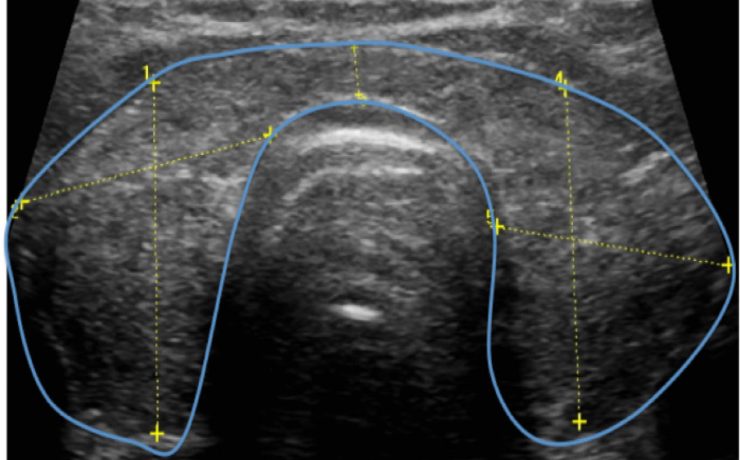

El síndrome de Rokitansky, es la anomalía más grave del tracto reproductivo femenino. Consiste en la ausencia congénita de vagina y útero ausente o rudimentario, como consecuencia de la falla en el desarrollo Mûlleriano de la vagina y el útero. Este síndrome fue descrito por Rokitansky en 1838. Es la